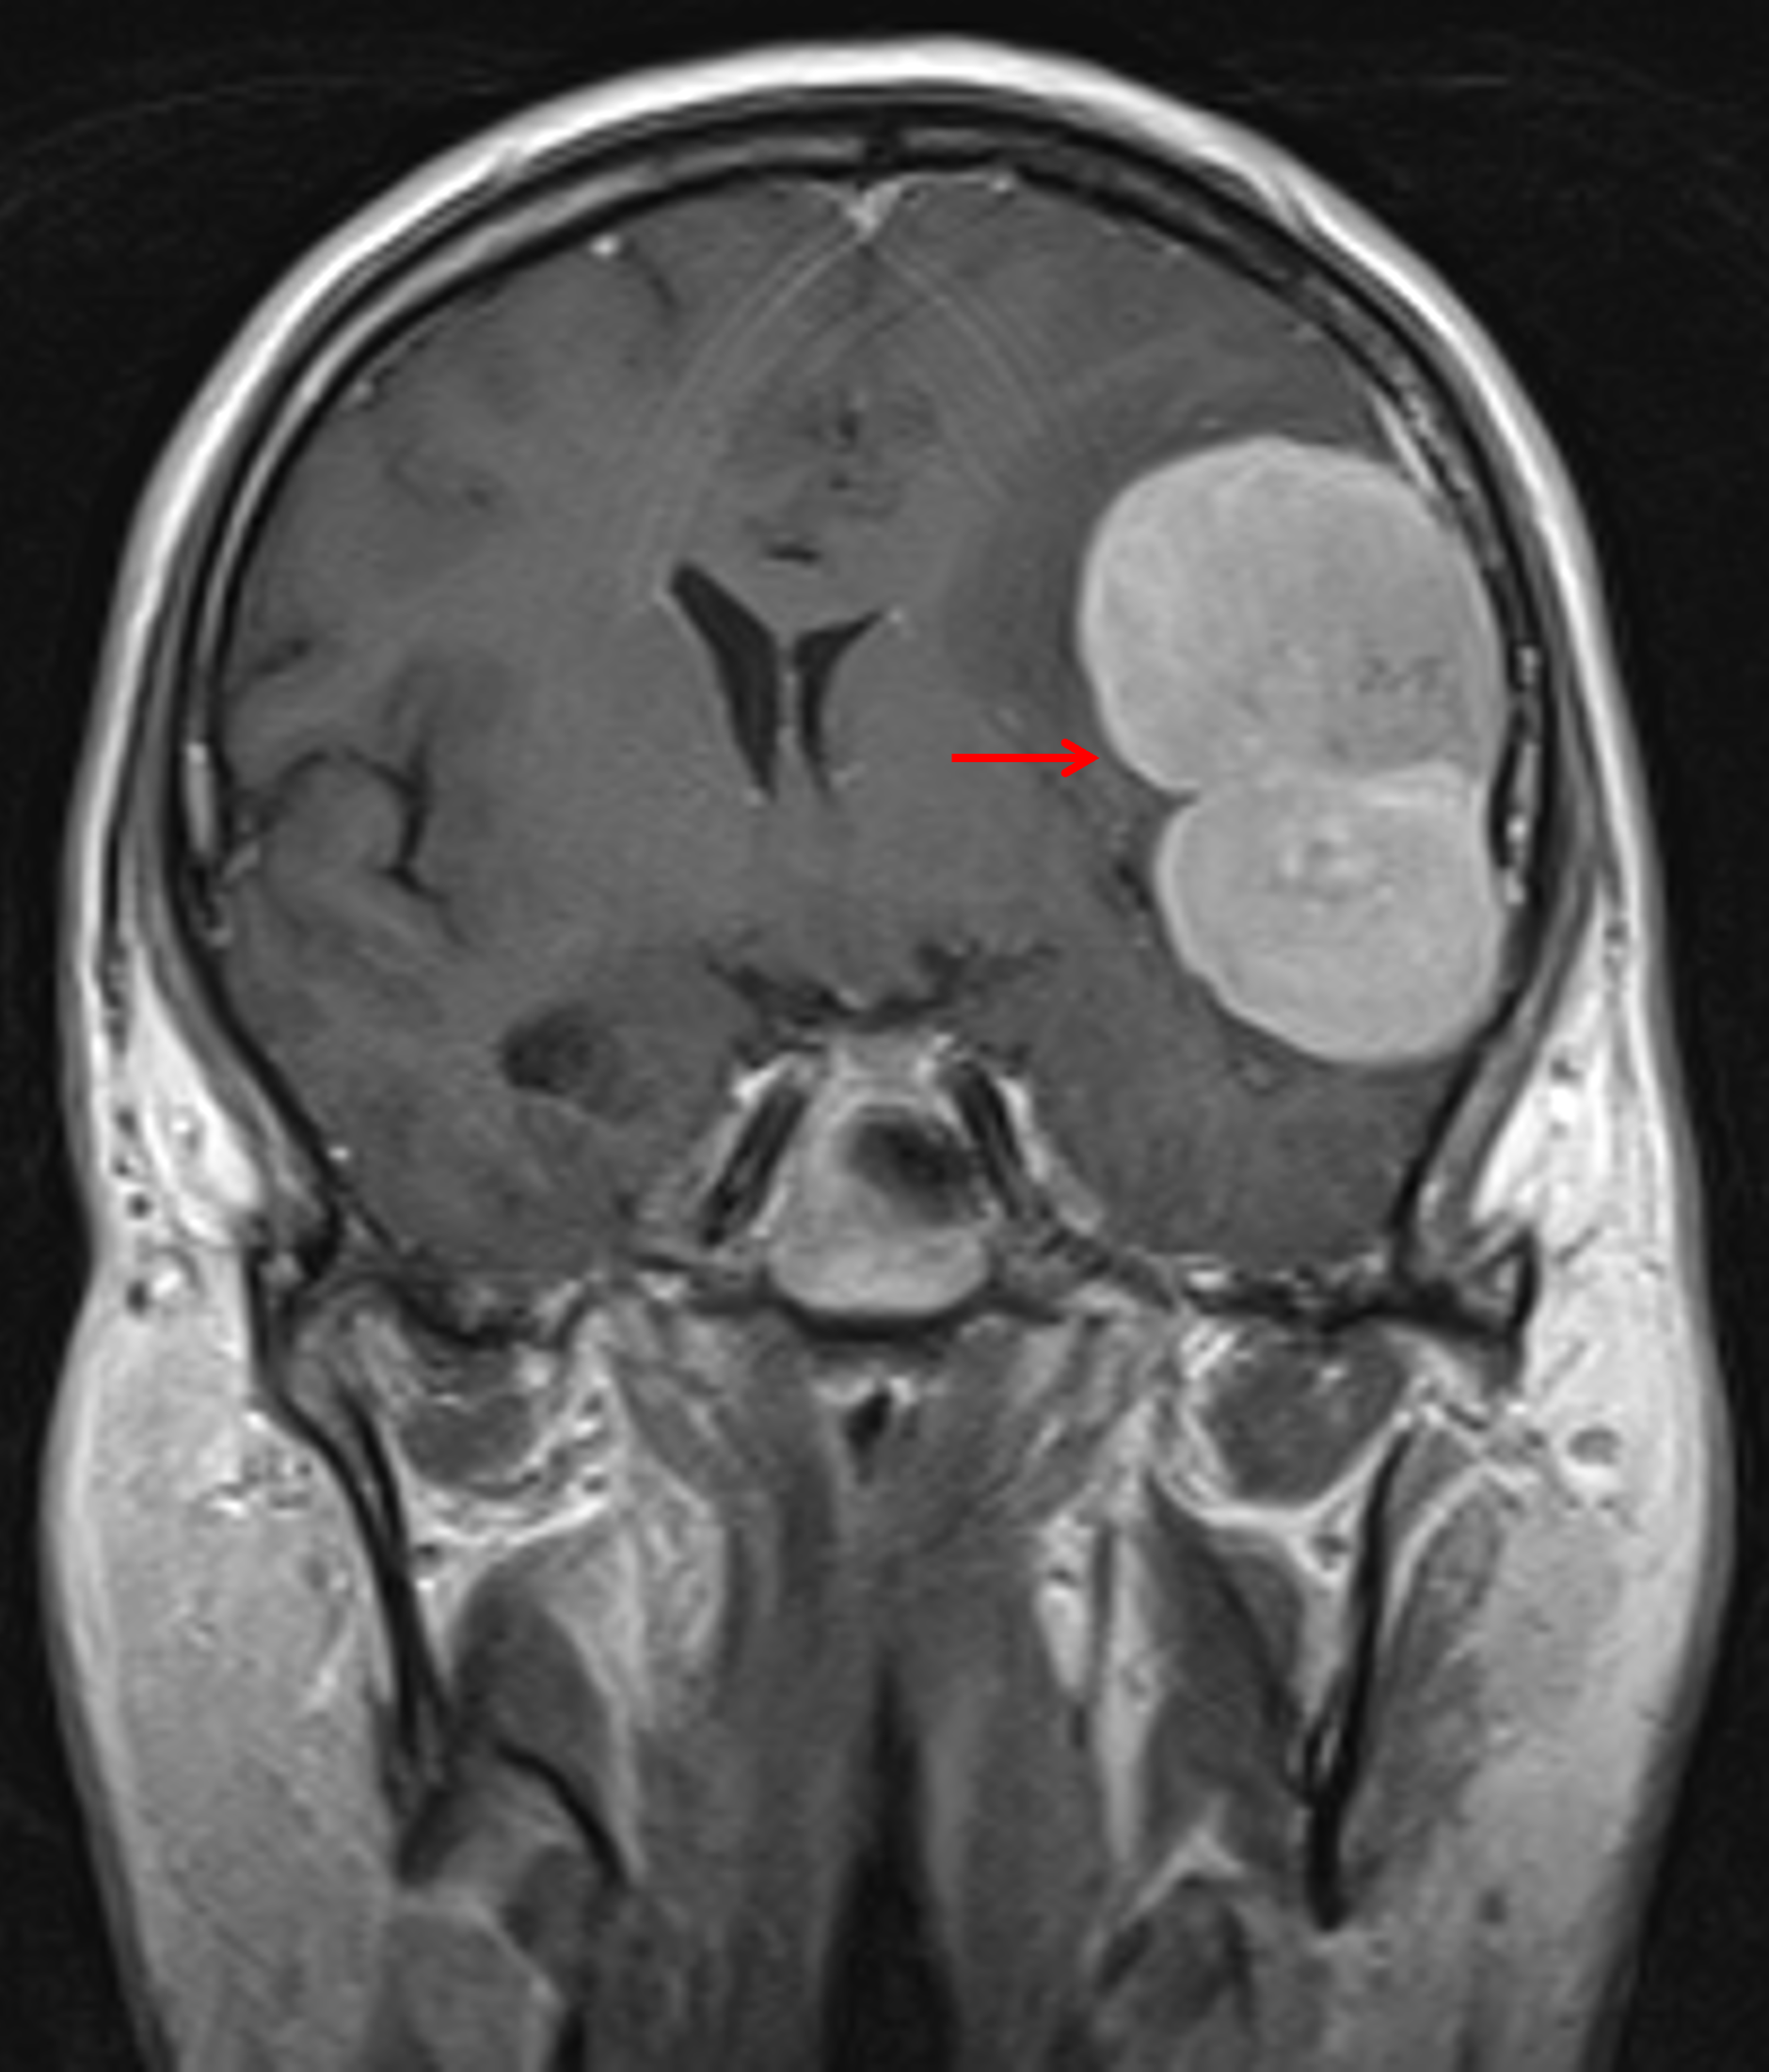

Age: 51

Sex: Male

Indication: Headache

MRI

Solitary fibrous tumor (hemangiopericytoma)